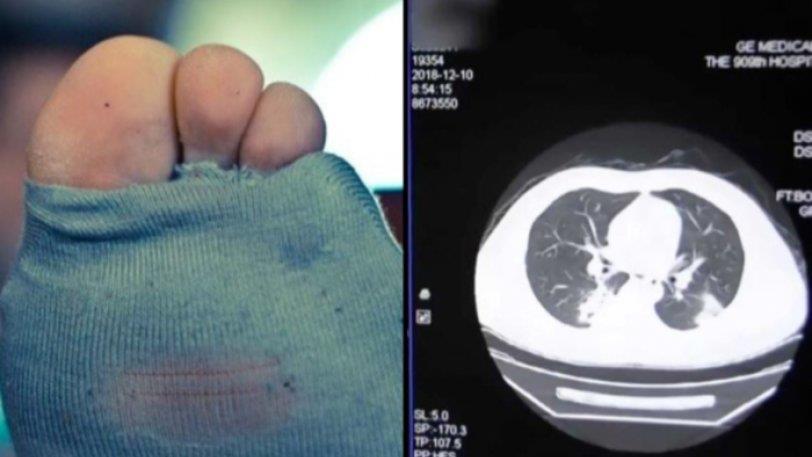

Η ακτινογραφία που υποβλήθηκε απέδειξε πως πάσχει από σοβαρή πνευμονική λοίμωξη και το νοσοκομείο επιβεβαίωσε πως ο λόγος ήταν η συνήθειά του.

Δεν ξέρουμε για πoιο λόγο λάτρευε να μυρίζει τις κάλτσες του, ωστόσο κατέληξε στο νοσοκομείο με λοίμωξη στους πνεύμονες.